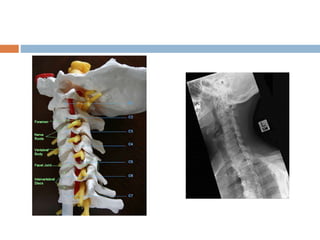

LATERAL PROJECTION (grandy method) Patientposition:  Place the patient in a lateral position either seated or standing.  Adjust the height of the cassette so that it is centered at the level of 4th cervical segment  Adjust the body in a true lateral position, with the long axis of cervical vertebrae parallel with plane of film  Elevate the chin slightly to prevent superimposition of mandible.  Ask the patient too look steadily at one spot on the wall to aid in maintaining the position of head  Respiration is suspended at end of full exhalation to obtain max depression of the shoulder.